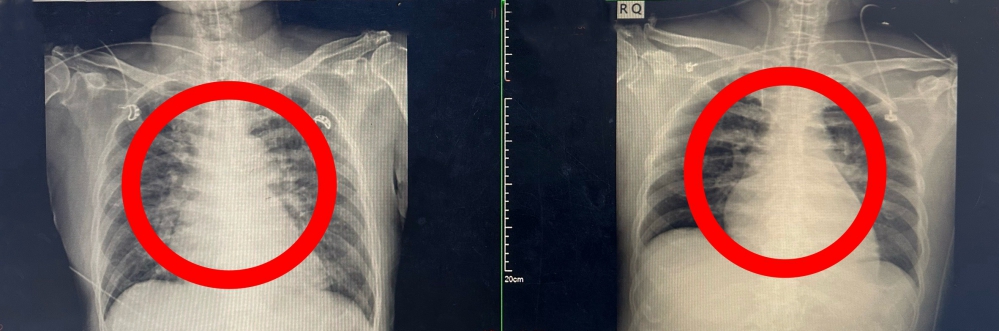

【記者林獻元台中報導】流感不只是感冒,嚴重時甚至可能奪命!衛生福利部豐原醫院日前收治一名七旬男性華叔,日前自國外旅遊返國後,陸續出現咳嗽與呼吸困難症狀,原以為只是一般感冒,未料短短數日內病情急轉直下,就醫檢查確診為A型流感,並迅速惡化為流感重症,併發急性心肌梗塞及心因性休克,導致心肺功能急遽衰退,生命徵象極度不穩,情況一度瀕臨死亡邊緣。豐原醫院16日表示,患者緊急入住加護病房後,立即啟動重症跨科整合醫療機制,由胸腔內科、心臟內科、心臟外科及腎臟科組成跨科搶救團隊。

豐原醫院指出,儘管第一時間已給予抗病毒藥物及呼吸與循環支持治療,患者仍出現心因性休克徵象,心肺功能持續惡化,心臟外科隨即決定啟動葉克膜(ECMO)治療,以暫時替代心肺功能,維持全身血液循環與氧氣供應,爭取黃金搶救時間。

在葉克膜支持下,心臟內科張偉俊醫師立即安排緊急心導管檢查,歷時7小時完成高難度冠狀動脈鈣化旋磨與震波氣球治療(Rota-Shock策略),成功打通三條嚴重阻塞之冠狀動脈並完成支架置放,同步放置主動脈內氣球幫浦(IABP),以提升心臟輸出量、減輕心臟負荷並穩定血流動力。